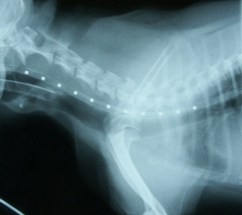

診断 気管虚脱GradeIV(図4)

図4 症例1の初診日。気管陰影ほぼ消失。